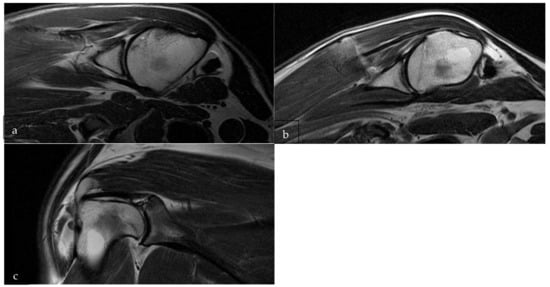

3.2. Post-Operative MRI Evaluation